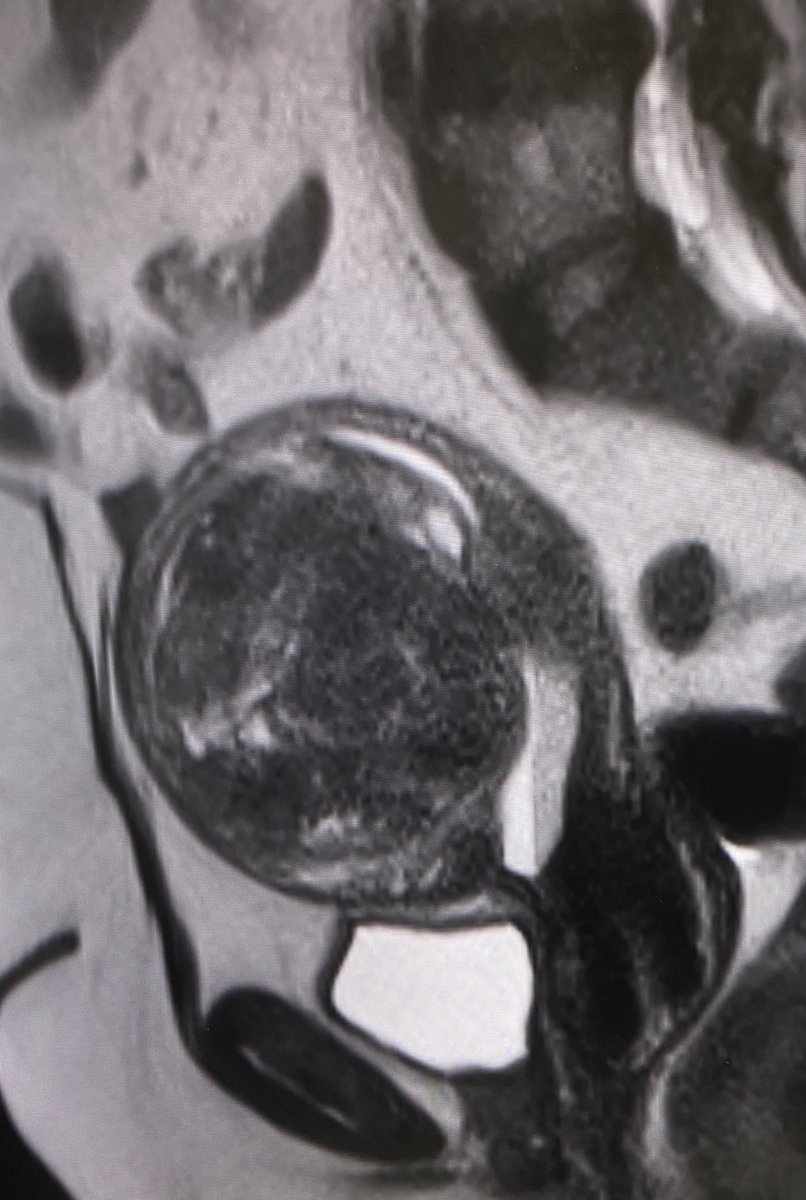

علاج أكياس البطانة المهاجرة او ما تسمى بأكياس "الشوكولاتة" بالقسطرة والأشعة التداخلية. اجراء بسيط جداً ، بدون تخدير كامل ، والأهم من ذلك كله؛ بدون التأثير على مخزون المبيض.